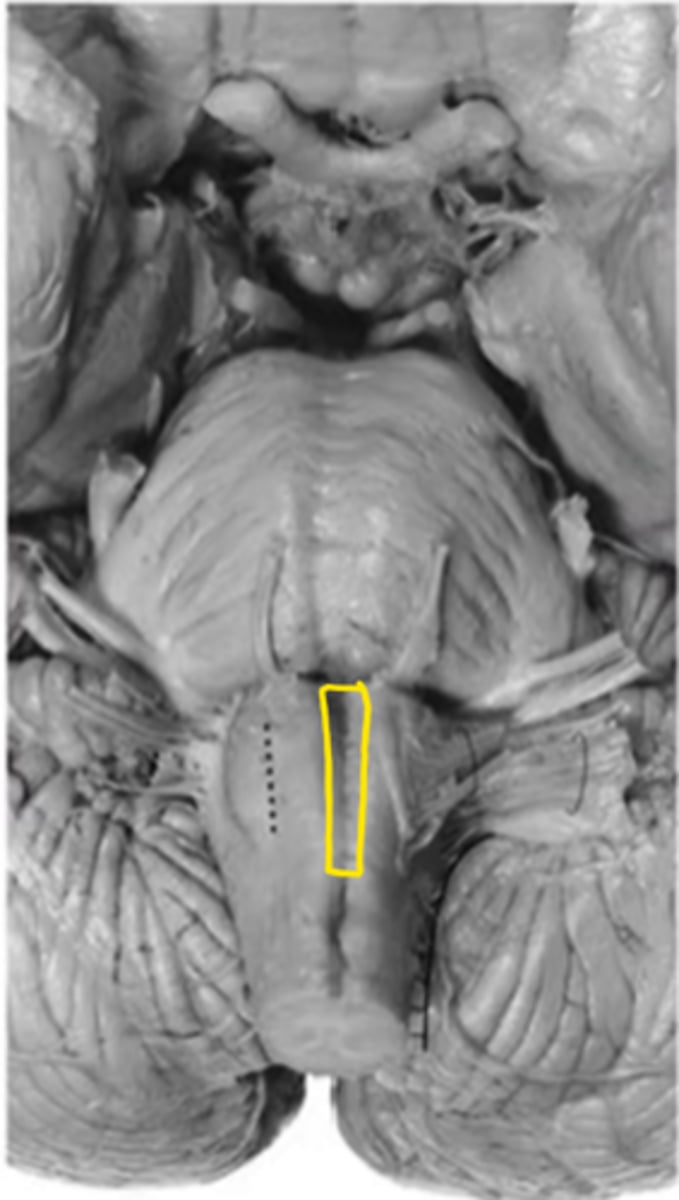

pyramidal decussation

ID the structure

motor decussation

closed medulla

ID the brainstem level